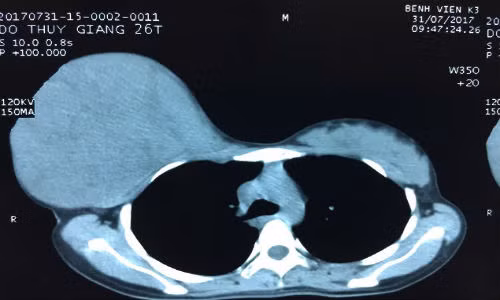

| Hình ảnh u tuyến vú rất to, chiếm toàn bộ tuyến vú phải của bệnh nhân G. |

Tại đây các bác sĩ khoa Ngoại Vú đã khám sơ bộ và chỉ định làm được làm các xét nghiệm đánh giá toàn trạng, chụp phim đánh giá tổn thương. Qua hình ảnh chụp phim cho thấy, u lớn chiếm toàn bộ tuyến vú phải của bệnh nhân.